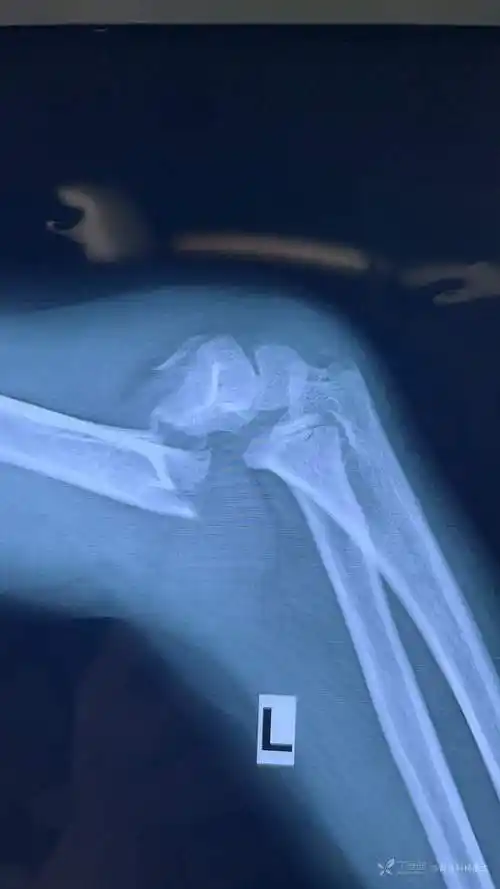

左侧肱骨髁上骨折一例

肱骨髁上粉碎性骨折,肱骨颈粉碎性骨折!

肱骨髁间骨折切开复位手术治疗